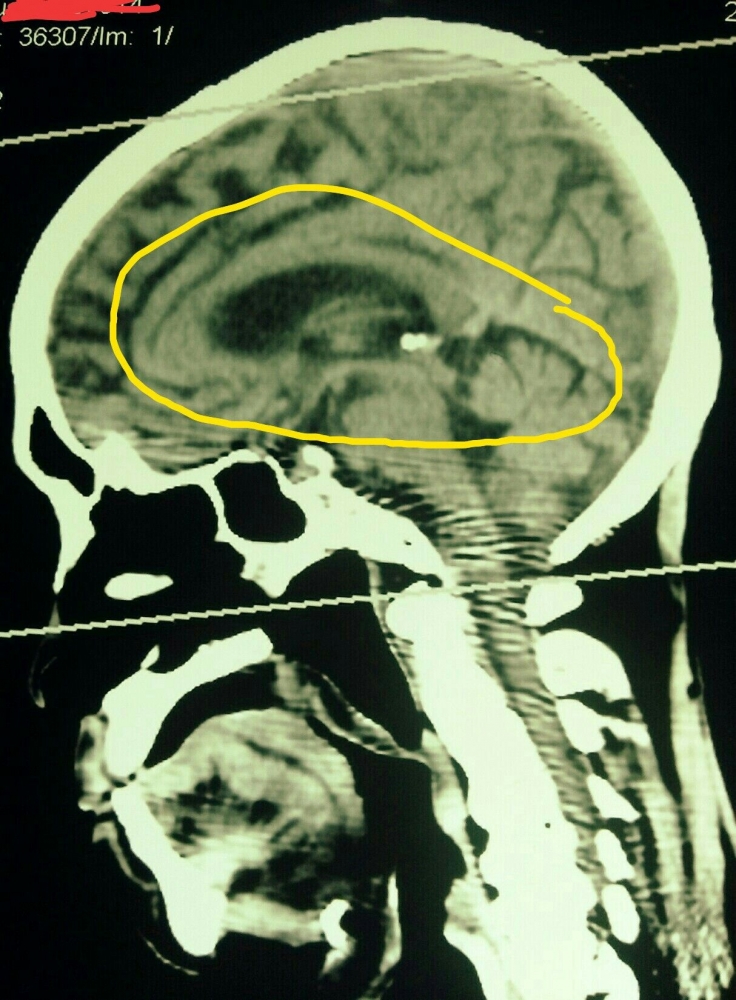

Fungsi luhur ada di tengah-tengah otak, biasanya mencakup ingatan, moralitas, kemampuan intelektual, emosi dan hal-hal yang bersifat kerohanian lainnya, biasanya akan tertekan kalau ada kurang lebih 100 cc pembengkakan di otak akibat adanya proses edema jaringan selama "stroke".